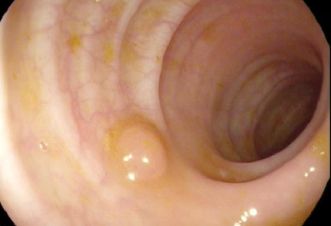

Magen Bei A-Gastritis kommt es häufig zur Bildung von neuroendokrinen Tumoren. Wenn diese <20mm sind, ist die Prognose gut. Einfach Abtragung ausreichend. 83-jährige Frau mit einem neuroendokrinen Tumor an der kleinen Kurvatur bei A-Gastritis.